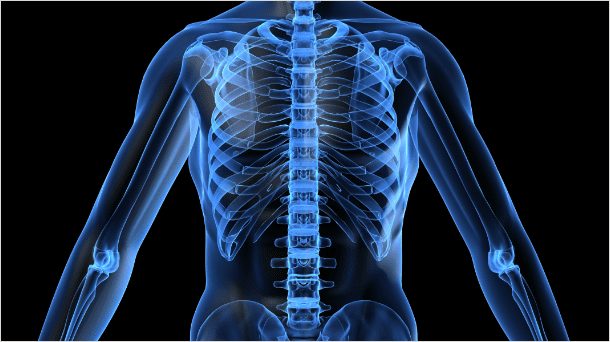

척추측만증,후만증,전만증

추의 만곡이 소실되어 척추가 왼쪽 혹은 오른쪽으로 휘어지는 증상을 척추측만증,

허리뼈가 아무런 굴곡없이 일자로 꼿꼿한 허리를 후만증, 앞쪽으로 휘어지는 증상을 전만증 이라고 합니다.

정상

비정상